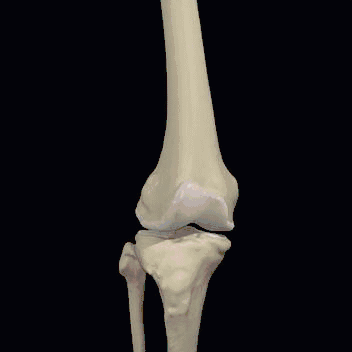

膝关节是人体中大而复杂的关节,它仅仅靠一个狭小的接触面支撑着我们整个身体的重量。